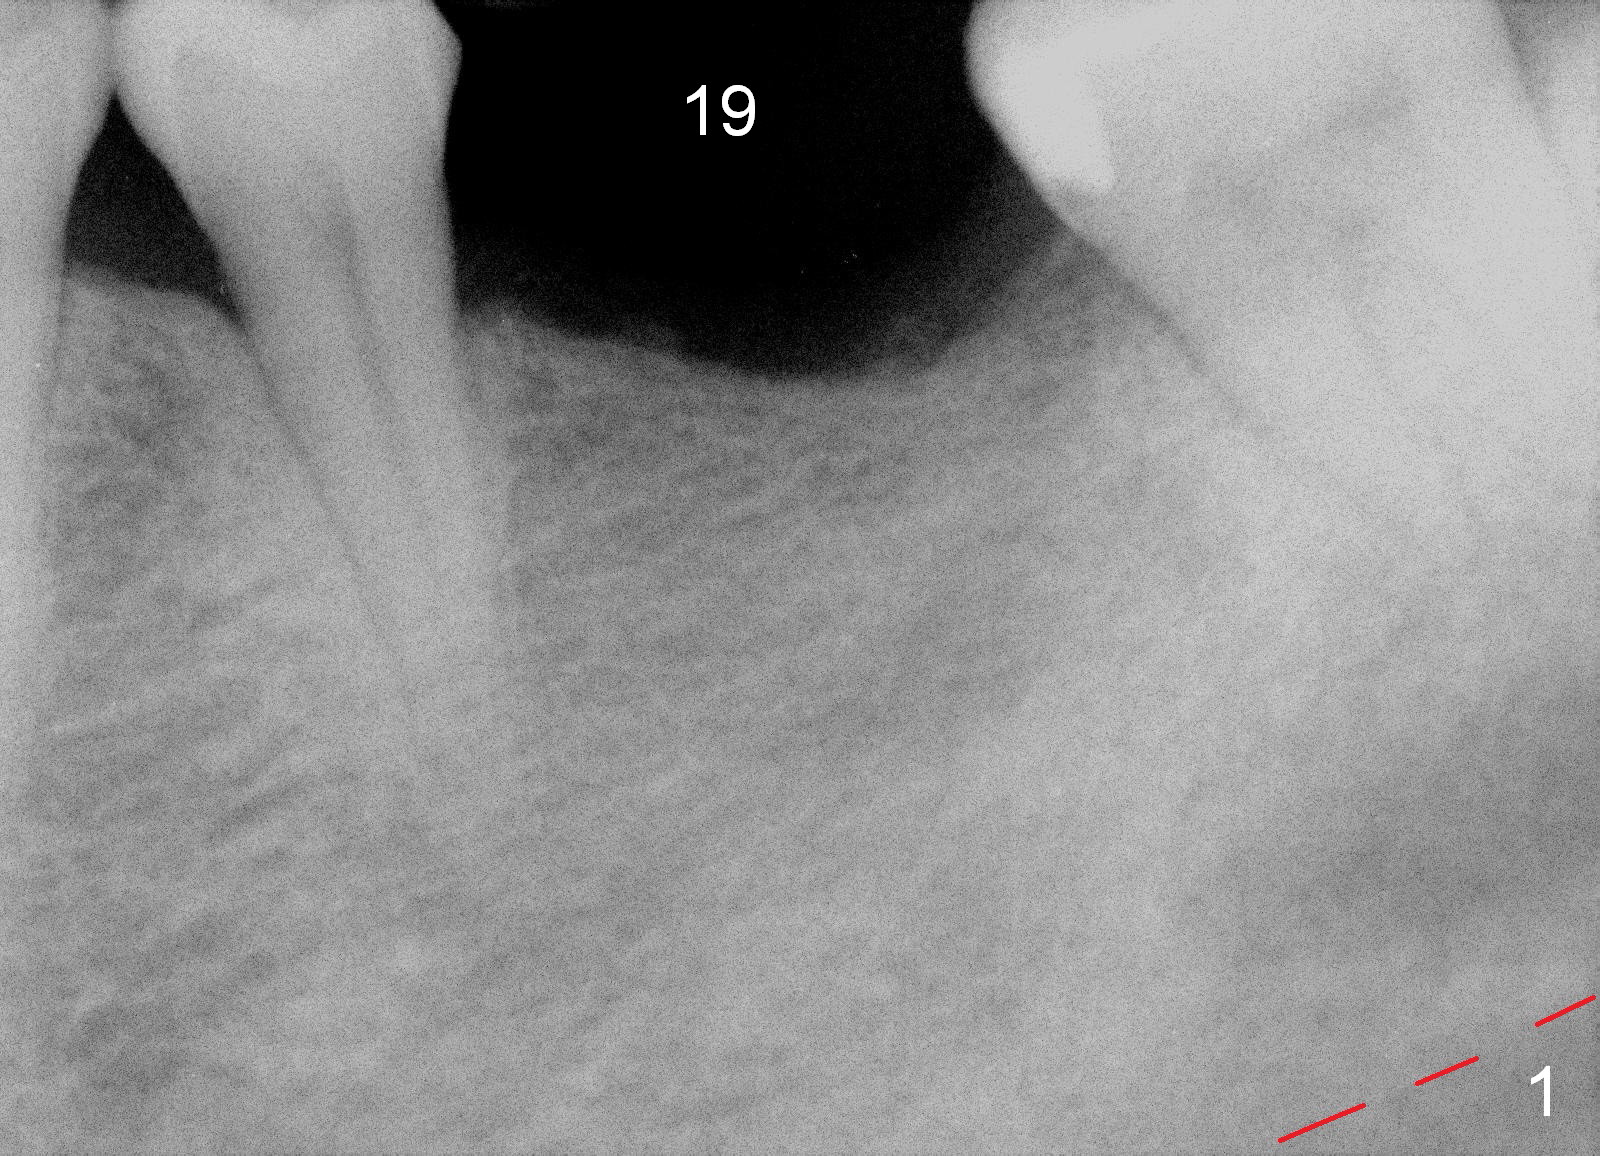

A 60-year-old man has lost the tooth #19 for approximate 20 years (Fig.1). The superior border of the Inferior Alveolar Canal is not distinct in PA. An implant that is slightly longer than the root of the neighboring tooth should be safe (Fig.2). Panoramic X-ray reveals plenty of bone height (Fig.3). Therefore, initial osteotomy depth will be 10 mm. Insert a parallel pin and take the 1st intraop PA for depth confirmation. If there is enough bone to place a 14 mm implant (Fig.4), but the crestal width is insufficient, place a 12 mm implant subcrestally to prevent thread exposure.